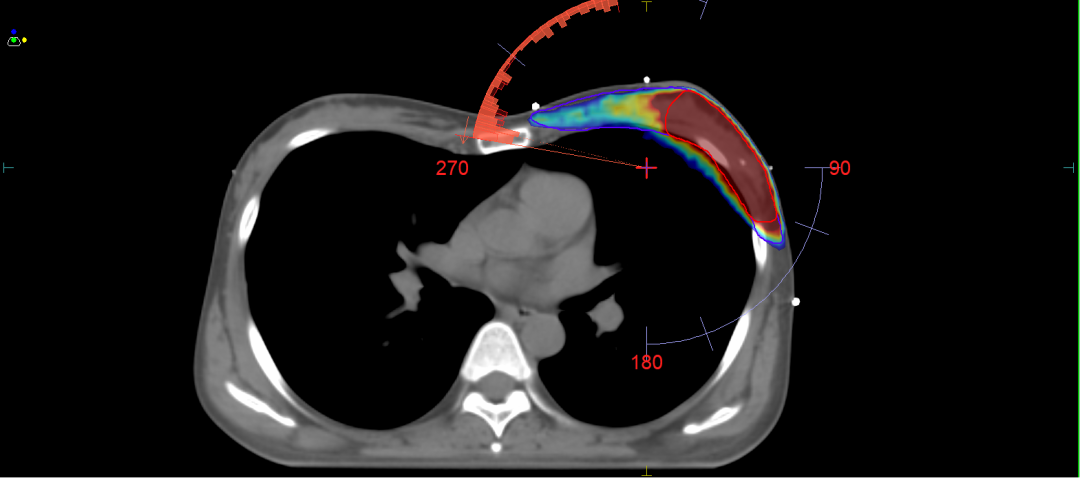

呼吸门控优化:DIBH技术有效减少乳腺癌患者放疗中心脏受照剂量达50%以上;

图2 深吸气屏气时,胸腔体积扩大,靶区远离心脏,减少心脏放射毒性。